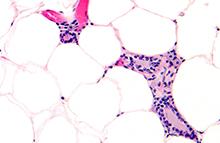

Integumentary System

Skin